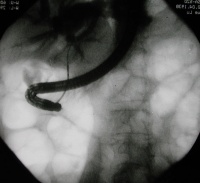

4.ERCP

通过内窥镜除可进行造影观察胰管的变化、结石的数目、大小、部位外,同时可进行胰液检查,以进一步了解有无恶变的可能。取胰液测CEA,若胰液的CEA活性<30ng/ml(同时血浆CEA<2.5ng/ml)则为阴性,若胰液CEA>30ng/ml(血浆CEA>2.5ng/ml),则要考虑阳性。应进一步检查如超声导向下细针穿刺细胞检查。通过胰管插管时(注胰泌素刺激后),收集胰液检查癌细胞,阳性率亦较高。

1.经内窥镜取石

此法仅用于胰管无狭窄的胰石。若无胰管狭窄可将括约肌切开取石,当结石较大时,可经超声碎石或

经内窥镜取石图像

激光震波碎石后取出。结石经过超声碎石后,结石破碎得较小,亦可自行排出。若胰管有狭窄因素存在结石虽经破碎取出,而梗阻因素并未解除,日后仍将形成结石。